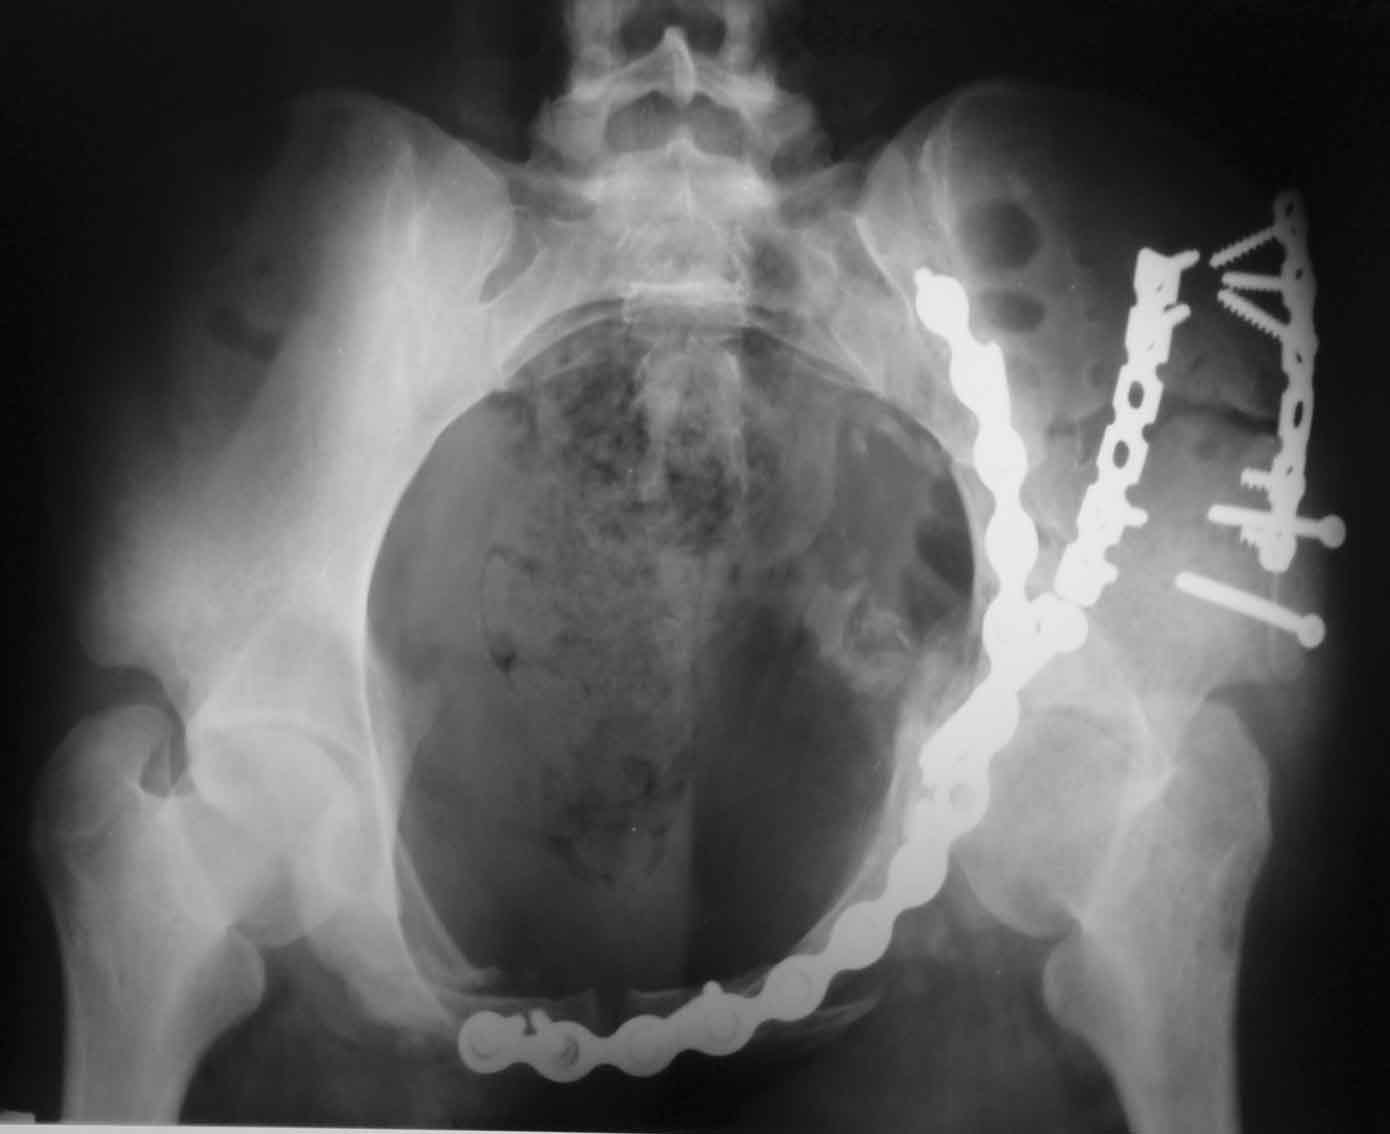

[Ortho] Рентгенограммы после операции

Inlet